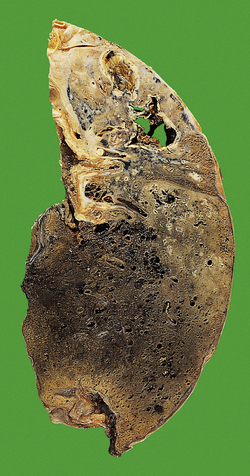

Pulmonary tuberculosis

image Lung is commonest site for tuberculosis

image Chronic alcoholism, diabetes mellitus, immunosuppression (especially HIV/AIDS), etc. are predisposing conditions

image Often reactivation of primary or secondary lesion

image A major cause of death in developing countries

Pulmonary tuberculosis (TB) is the leading cause of death globally from a single infectious agent; it has been estimated that a third of the world’s population has been infected with the organism. Most cases of pulmonary TB are the result of infection with M. tuberculosis although other so-called ‘atypical mycobacteria’ may be encountered (e.g. M. avian intracellulare, M. kansasii, etc.). The number with active disease is approximately 22 million, and about 1.66 million people die annually from TB.

Clinicopathological features

Clinical and pathological features of pulmonary tuberculosis are extremely variable, and depend on the extent, stage and activity of the disease (Fig. 14.10). Symptoms may vary from insidious weight loss with night sweats and a mild chronic cough, to rampant bronchopneumonia with fever, dyspnoea and respiratory distress (‘galloping consumption’). Most early cases of primary tuberculosis are clinically silent.

image

Fig. 14.10 Types of pulmonary tuberculosis. image Primary TB produces a small mid-zone lesion with involvement of hilar lymph nodes. image In secondary TB, the lesions are usually apical and often bilateral. image In miliary TB, the lungs and many other organs contain numerous small granulomas.